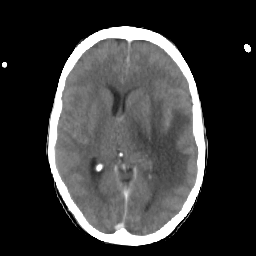

Metastatic bronchogenic carcinoma: Roentgen-ray CT -- Slice #11

[Home][Help][Clinical] Slice 11